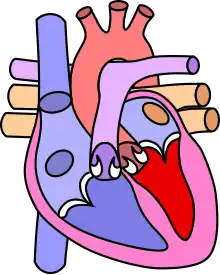

![]() | |

| Diagram of a healthy heart and one with tetralogy of Fallot | |

Tetralogy of Fallot (TOF), formerly known as Steno-Fallot tetralogy,[9] is a congenital heart defect characterized by four specific cardiac defects.[4] Classically, the four defects are:[4]

- Pulmonary stenosis, which is narrowing of the exit from the right ventricle;

- A ventricular septal defect, which is a hole allowing blood to flow between the two ventricles;

- Right ventricular hypertrophy, which is thickening of the right ventricular muscle; and

- an overriding aorta, which is where the aorta expands to allow blood from both ventricles to enter.

Four malformations

"Tetralogy" denotes four parts, here implying the syndrome's four anatomic defects.[2] This is not to be confused with the similarly named teratology, a field of medicine concerned with abnormal development and congenital malformations (including tetralogy of Fallot). Below are the four heart malformations that present together in tetralogy of Fallot:

| Pulmonary Infundibular Stenosis | A narrowing of the right ventricular outflow tract. It can occur at the pulmonary valve (valvular stenosis) or just below the pulmonary valve (infundibular stenosis).[4] Infundibular pulmonic stenosis is mostly caused by the overgrowth of the heart muscle wall (hypertrophy of the septoparietal trabeculae),[42] however, the events leading to the formation of the overriding aorta are also believed to be a cause. The pulmonic stenosis is the major cause of the malformations, with the other associated malformations acting as compensatory mechanisms to the pulmonic stenosis.[43] The degree of stenosis varies between individuals with TOF and is the primary determinant of symptoms and severity. This malformation is infrequently described as sub-pulmonary stenosis or subpulmonary obstruction.[44] |

| Overriding aorta | An aortic valve with biventricular connection, that is, it is situated above the ventricular septal defect and connected to both the right and the left ventricle. The degree to which the aorta is attached to the right ventricle is referred to as its degree of "override." The aortic root can be displaced toward the front (anteriorly) or directly above the septal defect, but it is always abnormally located to the right of the root of the pulmonary artery. The degree of override is extremely variable, with 5–95% of the valve being connected to the right ventricle.[42] |

| Ventricular septal defect (VSD) | A hole between the two bottom chambers (ventricles) of the heart. The defect is centered around the most superior aspect of the ventricular septum (the outlet septum), and in the majority of cases is single and large. In some cases, thickening of the septum (septal hypertrophy) can narrow the margins of the defect.[42] |

| Right ventricular hypertrophy | The right ventricle is more muscular than normal, causing a characteristic boot-shaped (coeur-en-sabot) appearance as seen by chest X-ray. Due to the misarrangement of the external ventricular septum, the right ventricular wall increases in size to deal with the increased obstruction to the right outflow tract. This feature is now generally agreed to be a secondary anomaly, as the level of hypertrophy tends to increase with age.[45] |